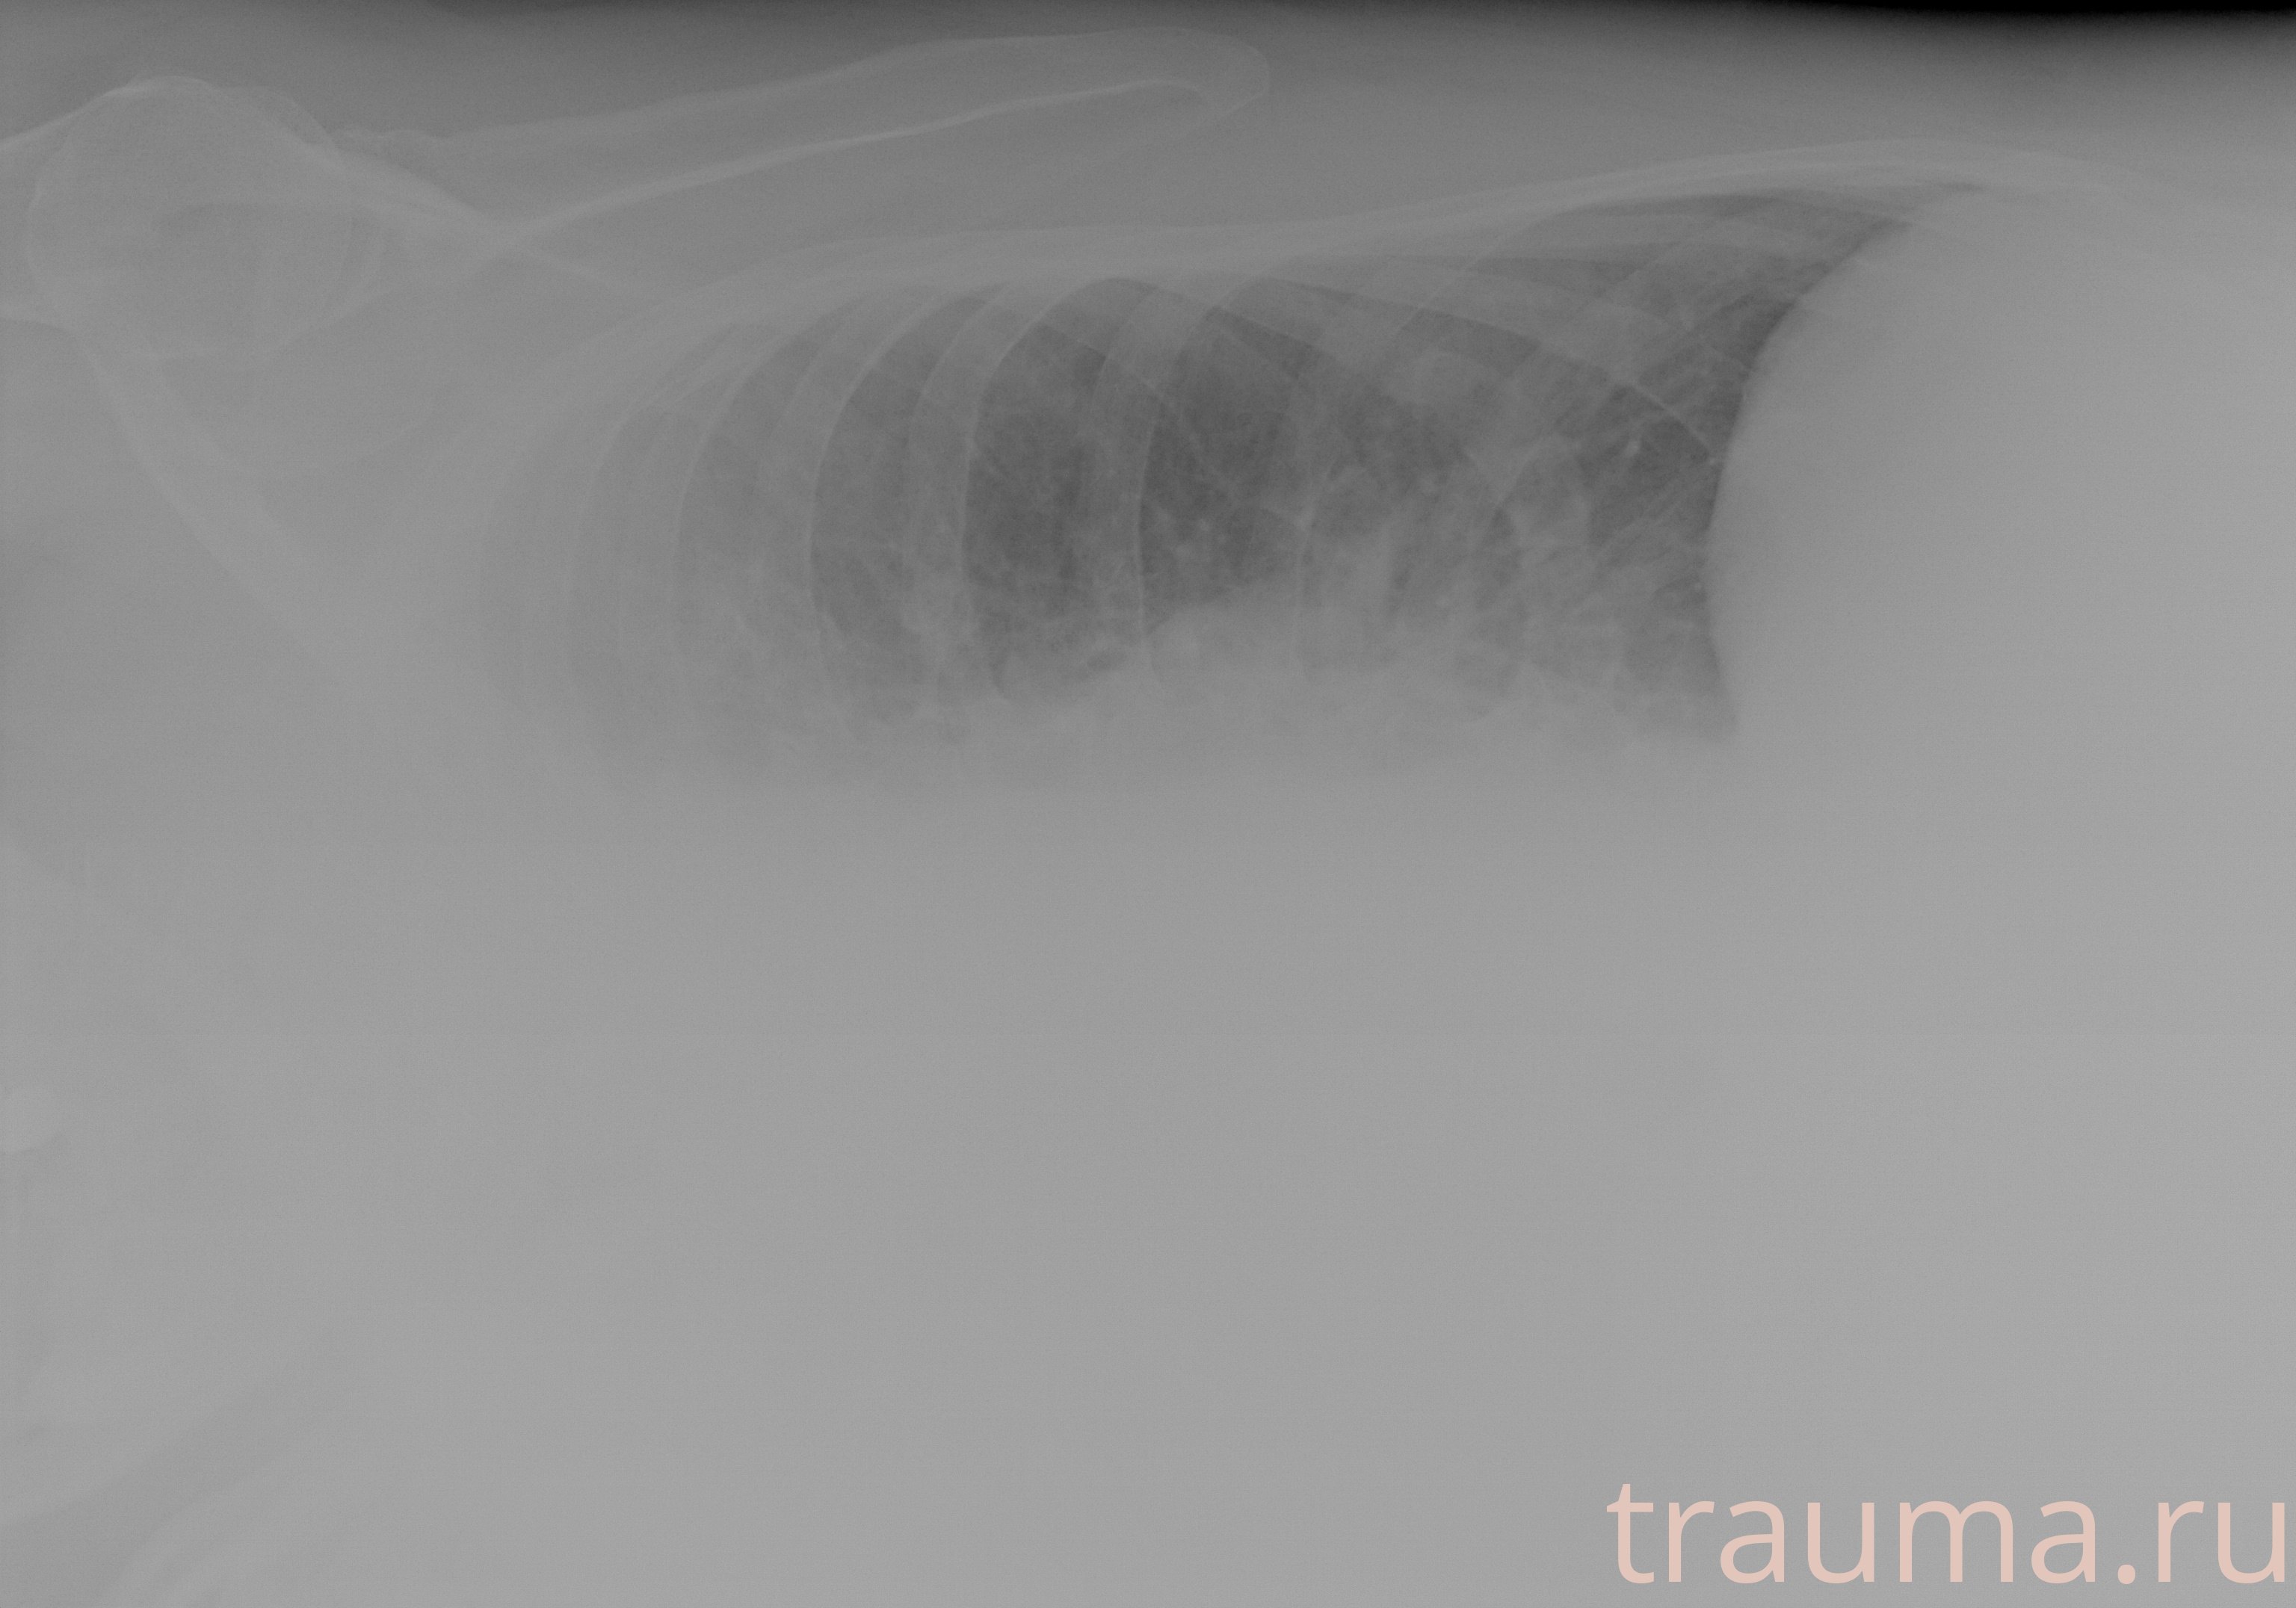

Рентгенограммы

Рентген на дому: по вашему адресу приезжает врач-рентгенолог, травматолог-ортопед с мобильным рентгеновским аппаратом, проводит диагностику травмы или заболевания, делает необходимые рентгенограммы, дает рекомендации по дальнейшему лечению. Получить качественные снимки в домашних условиях возможно благодаря уникальной методике, разработанной МосРентген Центром для института  Склифосовского

Яркость: 1   Контраст: 1   Инвертировать: 0 Увеличение: 1

Перетаскивайте мышь вверх/вниз для контраста, влево/право для яркости. Прокрутка колесом изменяет масштаб. Нажмите Сбросить для возврата к исходному изображению. При увеличении держите мышь в той области, которую хотите рассмотреть.